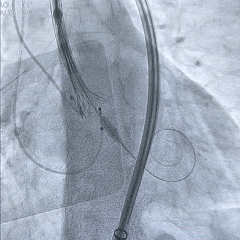

术中影像

根部造影:中大量反流,瓣叶活动度差

20mm球囊预扩:

轻微腰,无漏,左冠灌注正常

瓣膜0位初始定位

瓣膜稳定释放至全展开